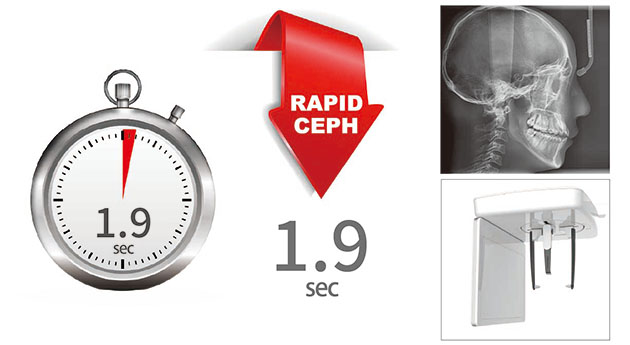

头颅侧位拍摄时间1.9秒

| 标准头颅侧位 | 1.9sec | |